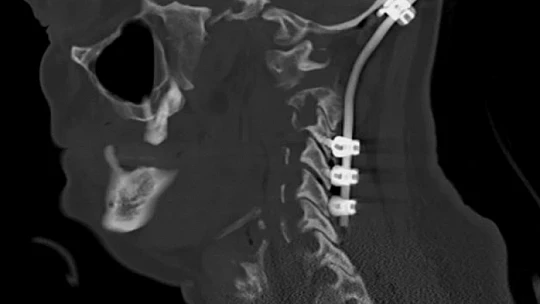

Ukrayna’da devam eden savaşta ülkede mahsur kalan Ahıska Türkleri, tahliye edilerek Elazığ’a getirilmiş ve Aşağıdemirtaş Geçici Konaklama Merkezine yerleştirilmişti. Burada yaşayan bir vatandaş, desteksiz yürüyememe ve boyun ağrıları şikayetleri ile Fethi Sekin Şehir Hastanesi Beyin Cerrahi Kliniğine müracaat etti. Hastanede ayrıntılı muayene ve tetkiklerde hastanın boynunda tümör olduğu saptandı. Beyin ve sinir cerrahisi kliniğinde başarıyla ameliyatı yapılan hasta, sağlığına kavuştu.

Beyin ve Sinir Cerrahisi Uzmanı Opr. Dr. Fatih Demir, “Boynundaki tümörün etkisiyle omurgada kırık ve açılanma gelişen hastamız ayakta durmakta güçlük çekiyor ve desteksiz yürüyemiyordu. Yaptığımız detaylı muayene ve tetkiklerle boynundaki tümörün hastadaki şikayetlere sebep olduğunu saptadık. Hastamızı ameliyat ederek baş ile boyun omurlarını sabitledik ve omuriliğe bası yapan tümörünü çıkardık. Başvurduğunda ayakta durmakta güçlük çeken ve desteksiz yürüyemeyen hastamızı yürüyerek taburcu ettik" dedi.